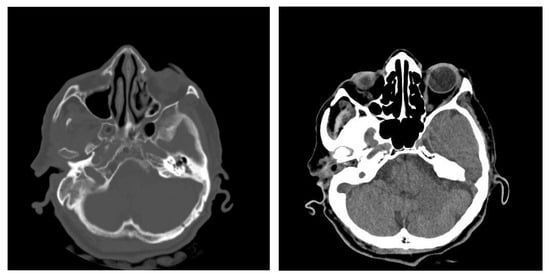

3.1.2. Computed Tomography and Magnetic Resonance Imaging

| CT Aspects | Number of Patients | Percentage |

|---|---|---|

| Fluid accumulation | 168 | 100% |

| Osteolysis | 152 | 90.47% |

| Osteocondensations | 128 | 76.19% |

| Cholesteatoma | 48 | 28.57% |

| Exocranial extensions | 48 | 28.57% |

| Intracranial extensions | 24 | 14.28% |

| Changes to the external auditory canal | 68 | 40.47% |

| Ossicular chain damage | 144 | 85.71% |